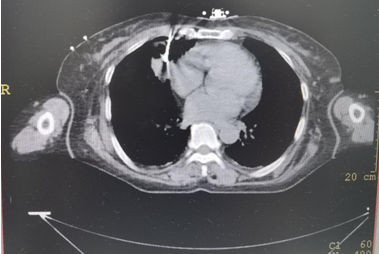

▲上图:穿刺到位